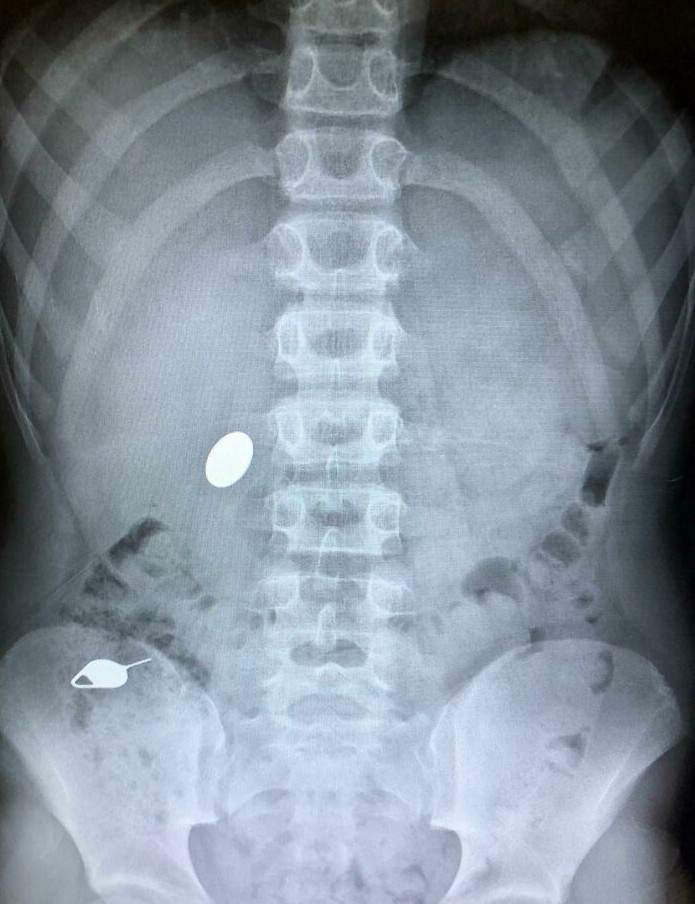

▼小朋友就是要注意,不然很多東西都愛往嘴裡塞

圖片來自:reddit